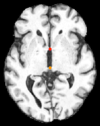

Datasets: A set of isotropic mm MR scans were obtained from the ADNI database [10] to evaluate the proposed method. While, a subset of and images are used for training and testing. All brain images were skull stripped and affinely aligned to the MNI space, thus allowing ground truth planes to be extracted in the standard directions. For cardiac images, we use short-axis cardiac MR of resolution mm obtained from the UK Digital Heart Project [8]. A subset of and images are used for training and testing. ACPC planes are evaluated using the AC and PC landmarks for the distance error calculation. Similarly, we use the outer aspect, inferior tip and inner aspect points of splenium of corpus callosum for mid-sagittal planes. For cardiac MRI, we use six landmarks projected on the 4-chamber plane; the two right ventricle (RV) insertion points, right and left ventricles (LV) lateral wall turning points, apex, and the center of the mitral valve, See Fig. 2.

Results: During inference, the environment samples a plane and the agent updates sequentially new plane’s parameters until reaching the terminal state. In order to have a fair comparison between different variants of the proposed method, we fix the initial plane for all models during evaluation. Table 1 shows the results from these comparative experiments. All methods share similar performance including speed and accuracy, and there is no unique winner for the best overall method. Best performing agents for detecting the mid-sagittal and ACPC planes achieve accuracy of mm and , and mm and , respectively. Where in cardiac, the task is more complex due to the lower quality and higher variability between different scans. The agent has to navigate in a bigger field of view compared to brain images. Thus Duel DQN-based architectures achieve the best results for detecting the 4-chamber plane with mm and accuracy, as a result from learning a better state value function by decoupling it from action-value function. These results are better than the state-of-the-art [6], which achieves an accuracy of mm and . Unlike [6], our method does not require manual annotation of landmarks. More visualization results are published on our github.